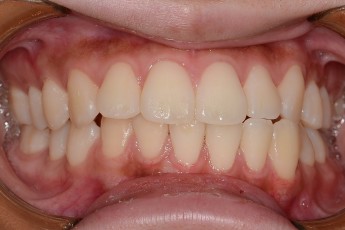

BEFORE & AFTER